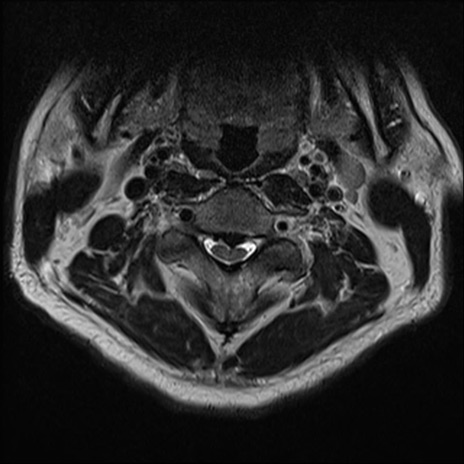

【整形】TIPS症例7 頚椎MRI T2WI(横断像)

頚椎MRI

矢状断像と横断像